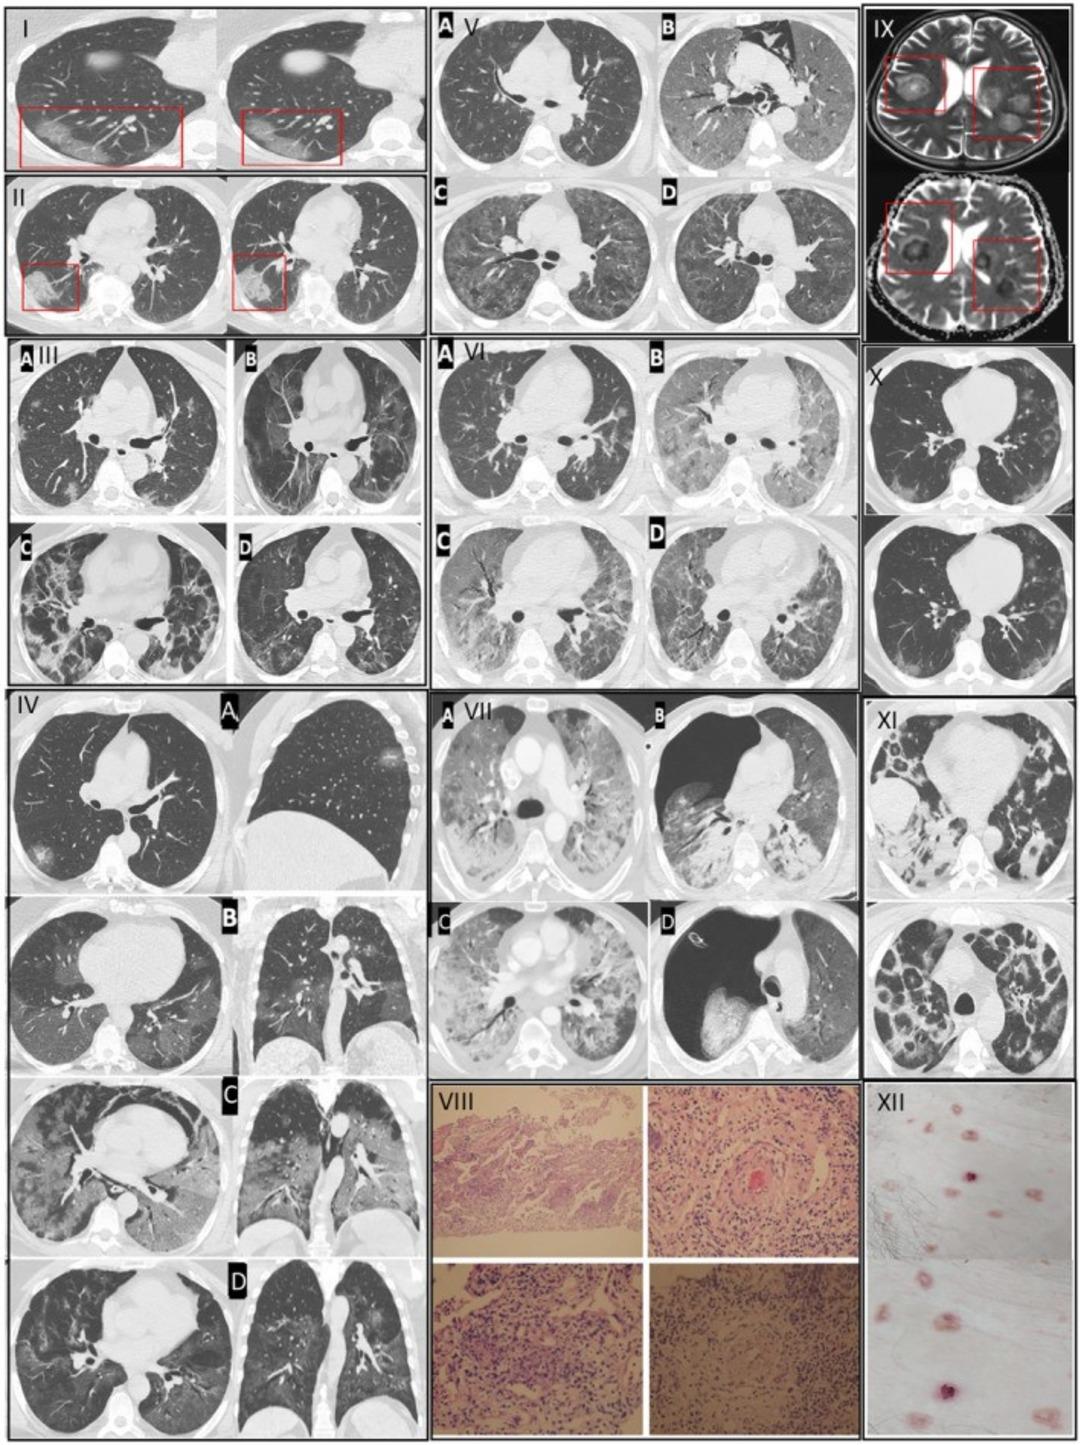

"5 YILLIK YAŞLANMAYA EŞDEĞER"Prof. Dr. Özkaya, Kovid-19'un özellikle kılcal damar düzeyinde ciddi hasar bıraktığını belirterek, "Pandemi boyunca takip ettiğimiz binlerce hastada ‘endotelit’ dediğimiz damar iç yüzeyi hasarının ani ölümleri tetiklediğini saptadık ve uluslararası dergilerde yayınladık. Avrupa Kalp Dergisi’nin son verilerinde de bu durum ‘Kovid-19 sonrası damar yaşlanmasının hızlanması’ olarak tanımlanmıştır. Virüsü geçirenlerde damar yaşı, takvim yaşından daha yaşlı hale geliyor. Bu etki bazı kişilerde 5 yıllık yaşlanmaya eşdeğer" dedi.

Özkaya, Kovid-19 sonrasında yoğun egzersiz yapan gençlerde ani kalp krizlerinin görülebildiğini belirterek şunları söyledi: "Pandemi öncesi yaptığı ağır sporları aynı şekilde sürdüren bazı kişilerde ciddi kalp ve akciğer sorunları ortaya çıkabiliyor. Kovid-19 sonrası kalp ve akciğer kılcal damarlarındaki hasar nedeniyle ağır egzersiz sırasında vücut yeterli oksijenlenmeyi sağlayamıyor; bu durum ani ölüme kadar gidebiliyor."